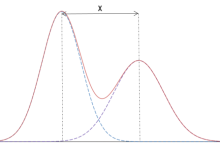

光子计数探测器由碲镉(CdTe)、碲锌镉(CZT)或硅(Si)等半导体制成。由于原子序数较高,碲化镉和碲锌镉层可以相对较薄(1.4-2mm),但仍能提供较高的X射线吸收率。而由硅制成的光子计数探测器则需要更厚(30-60mm)才能充分吸收X射线。根据目前的文献,所有临床前或临床使用的PCD-CT都配备了碲化镉或碲锌镉探测器。图1显示了基于碲化镉或碲锌镉的PCD的结构示意图。在半导体层的上侧是一个大面积的阴极电极,在下侧为像素化阳极电极。在阴极和单个阳极之间施加800-1000 V的高压,可产生强大的电场。入射的X射线被半导体吸收,产生的电荷(电子-空穴对)在电场中分离。电子移动到阳极,在那里产生持续时间约为1 ns(109 s)的短电流脉冲,通过电子脉冲整形电路转换成半宽(FWHM)为10-15 ns的电压脉冲。电压脉冲的脉冲高度与X射线的吸收能量E成正比。一旦脉冲超过阈值TL,即吸收能量(通常为20-25 keV),读出电子装置就会对其进行计数。在技术实现中,使用了一个脉冲高度比较器电路,其中输入了与阈值能量相对应的电压,参见图1。探测器信号相当于在投影测量时间内记录的所有脉冲的总和。

图1 CdTe/CZT PCD(上图)和相应读出ASIC(下图)的示意图。从CT系统的正面看,扇形方向是沿探测器扇形扫描平面的方向。单个探测器像素是由公共阴极和像素化阳极(此处用虚线表示)之间的强电场形成的;像素之间无需进一步分离。在本图所示的探测器结构中,两个准直器叶片之间各有4个子像素,用于抑制散射辐射,另见图4。在ASIC中,被吸收的X射线量子产生的电压脉冲在脉冲高度比较器中与对应于所需阈值能量(20-25 keV)的阈值电压进行比较。只有超过该阈值能量的X射线量子才会被计数。

为了获得光谱分辨数据,需要同时读出在不同阈值能量下工作的多个计数器,见图2。然后,探测器为每个阈值提供单独的数据流,其中只包含能量超过相应阈值能量的X射线量子,另见图2。从包含能量超过最低阈值能量TL的所有X射线量子的数据流中重建的图像(TL图像,西门子公司专有,也称为T3D图像)可与传统CT在相同的X射线管电压(kVp)下获得的图像相媲美。然而,在现实的PCD中,由于不可避免的物理效应降低了信号的光谱分离度,如像素边界的电荷共享或荧光导致的X射线量子能量损失,能量登记存在误差。这些效应的示意图如图3所示,它们会导致量子在X射线能量过低时被错误地计数两次。与CdTe-PCD或CZT-PCD相比,硅PCD受电荷共享和荧光的影响较小,因此光谱分离效果较好,但大多数X射线量子主要在硅晶体中散射,而不是直接吸收;它们经常离开探测器像素而不产生信号,因此探测器的探测量子效率降低,所有探测任务都需要更高的辐射剂量。在非常高的X射线通量下,产生的电压脉冲在时间上重叠,不再单独计数。然而,在实际的CT通量率下,脉冲堆积并不起作用。

图2 使用PCD采集光谱数据的示意图。上图所示为吸收不同能量的X射线量子所产生的电压脉冲时间序列。下图是一个4门限计数器的技术实现示意图。在此示例中,同时读出4个计数器的阈值能量分别为20、35、60和75 keV。探测器提供4个原始数据流,其中只包含吸收能量大于各自阈值能量的计数X射线量子。

图3 电荷共享和K-escape的示意图,它们降低了现实PCD的能量分离。靠近像素边界吸收的X射线会产生电子,这些电子会在相邻像素中产生信号(电荷共享)。因此,一个X射线光子会以过低的能量被错误地计数多次。入射的X射线最初还会击穿探测器材料的内壳电子(K电子)。这会产生荧光辐射,荧光辐射会被探测器单元本身或邻近的探测器单元重新吸收和计数(K-逃逸)。入射到初级相互作用位点的X射线以过低的能量进行计数。